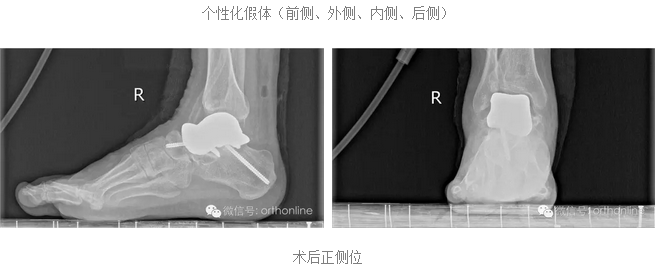

个性化距骨假体突显生物学功能重建:

除了具有3D打印构建的支撑作用外,还对假体进行了结构差异化设计,具有更为优质的结构承重功能;

假体关节面材料经过特殊处理,除了关节接触耦合好、摩擦小等特点,更重要的是假体的弹性模量与人体更为接近,大大提高了耐磨性;

突破传统的3D打印假体的界面处理方法,采用假体界面微孔打印等方法,更有利于骨组织长入。

假体个性化特性更为明显:

假体制作完全忠实于患者个体的解剖结构,术前将健侧的骨性解剖数据进行镜像处理,获得个性化假体数据源;3D打印完成后再将假体扫描,与数据源进行耦合对照检测;假体植入后扫描患肢,检测与数据源耦合性能;

塌陷性距骨坏死一直是踝关节假体置换的绝对禁忌症,该假体打破了常规,为塌陷性距骨坏死提供了非常好的选择。